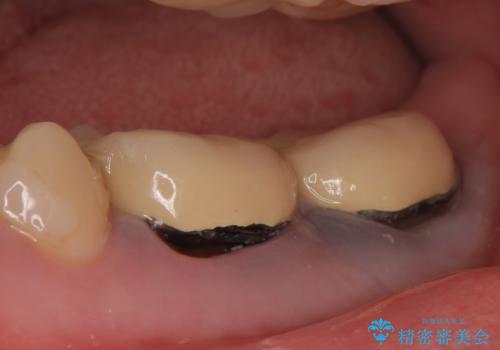

- 右下奥歯の歯茎がよく腫れるので診て欲しいといらっしゃった方の症例です。

診査の結果、右下6番目の根尖病変を認めたため再根管治療を行いました。

また右下7も根管充填が不十分なため再根管治療を行いました。